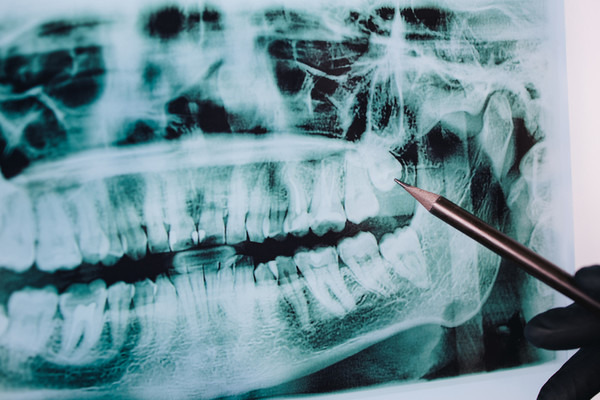

사랑니 발치 후 붓는 이유

사랑니는 일반 치아보다 큰 경우가 많습니다.

게다가 잇몸 깊숙한 곳에 있어요.

큰 치아가 깊숙한 곳에 단단히 박혀있으니,

이런 치아를 뽑아내려면

주변 조직에 자극이 가해질 수밖에 없죠.

부종이 심할 수밖에 없는

매복 사랑니 발치의 경우에서 자주 나타나요.